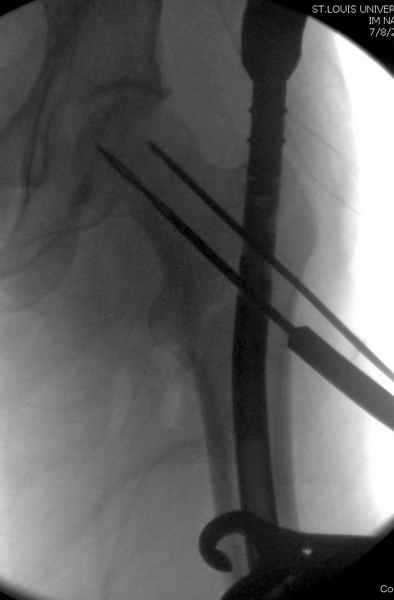

Как раз недавно у меня был примерный случай: больному 36 лет, поступил ночью, травма в результате мотоциклетной аварии, кроме чрезвертельного и спирального перелома левого бедра имеется переломы костей предплечья с этой же стороны. Скелетное вытяжение, а на следующий день больной про оперирован на ортопедическом столе с дистракцией. Чтобы не расколоть чрезвертельный перелом провели временную спицу ближе к переднему кортексу, из малого разреза костодержатель для репозиции, а фиксацию провели антиградным штифтом. Этапы операции на снимках.

DK> фиксацию провели антеградным штифтом.

Да, сейчас это и у нас самый напрашивающийся выбор. Сделали гвоздем ChM, картинки в приложении.